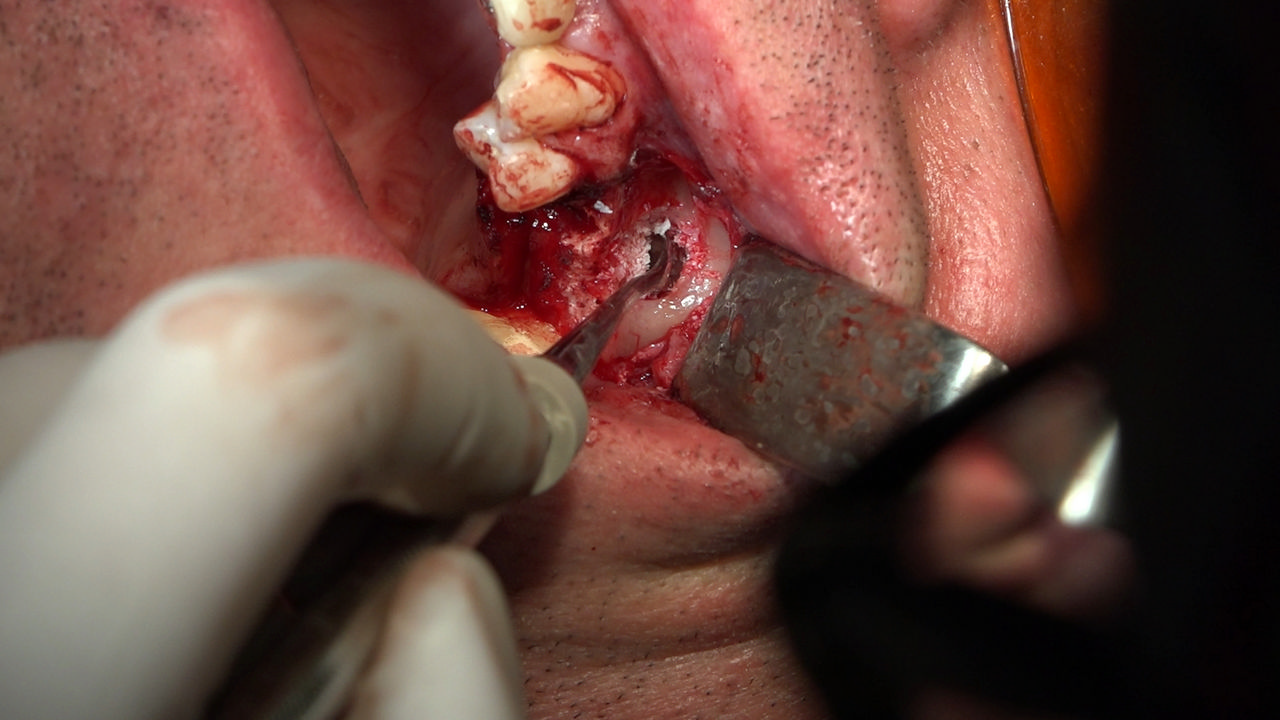

7 Sesja X Sezonu Practiculum Implantologii, w której brali udział kursanci z Grupy A i B, obejmowała implantacje wykonane systemem Axiom, procedury regeneracyjne tkanki kostnej i zabieg sinus lift oraz procedury implantoptotetyczne. Ten zakres szkolenia poprowadziła dr Małgorzata Piotrowska. Protetyka na implantach, to finalny etap leczenia implantologicznego decydujący o uzyskaniu harmonijnego łuku zębowego, okluzji oraz szczelności połączeń, a więc zadowoleniu Pacjenta i powodzeniu całego procesu leczenia.

Jego sednem jest wybór optymalnego rozwiązania rekonstrukcji protetycznej uwzględniający bardzo wiele czynników o charakterze mechanicznym, funkcjonalnym i estetycznym, związanych ze stanem tkanki kostnej, jamy ustnej i uzębienia. Odbywa się już na etapie tomografii komputerowej i jest ściśle powiązany z częścią chirurgiczną, ponieważ prawidłowe zaplanowanie pracy i usytuowania implantów wspomagane plastyką tkanek miękkich, to dla procedur protetycznych baza wyjściowa. Zasady te są jak najbardziej oczywiste, zarówno przy samodzielnym wykonywaniu leczenia implantologicznego, jak i przy podziale zadań dla chirurga i protetyka, czyli pracy w duecie.